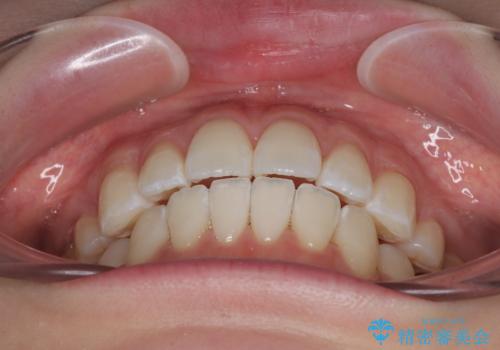

飛び出した前歯を引っ込める ワイヤー装置での抜歯矯正治療

- くちばしのように飛び出した前歯を気にして来院された患者様です。

上下左右の第一小臼歯4本を抜歯して、ワイヤー装置にて矯正治療を行うこととしました。

舌の突出癖により、口元が突出しているだけでなく、上下前歯が非接触となっておりました。

舌のトレーニングをしっかりと行っていただくことで、2年を切って治療を終えるとともに

、上下前歯を接触させることができました。